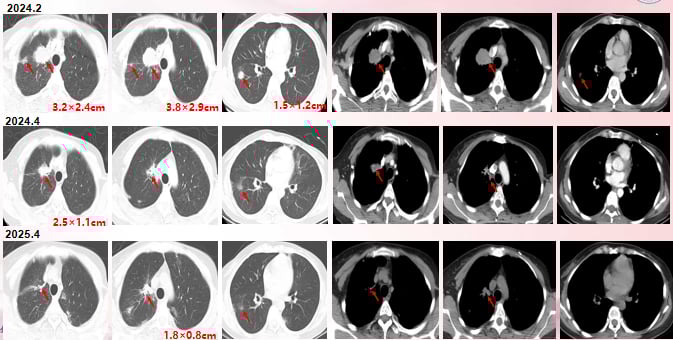

- 影像学缓解: CT和MRI复查显示,肺部、淋巴结等病灶显著缩小,达到了部分缓解(PR)。

尽管T-DXd疗效显著,但患者近期影像提示肺部、骨骼和肝脏可能出现新发微小病灶。专家建议,后续治疗需密切监测颅内病灶情况,并综合评估患者全身状况,可考虑的选项包括更换ADC药物、联合小分子TKI药物或再次尝试靶向联合内分泌治疗。